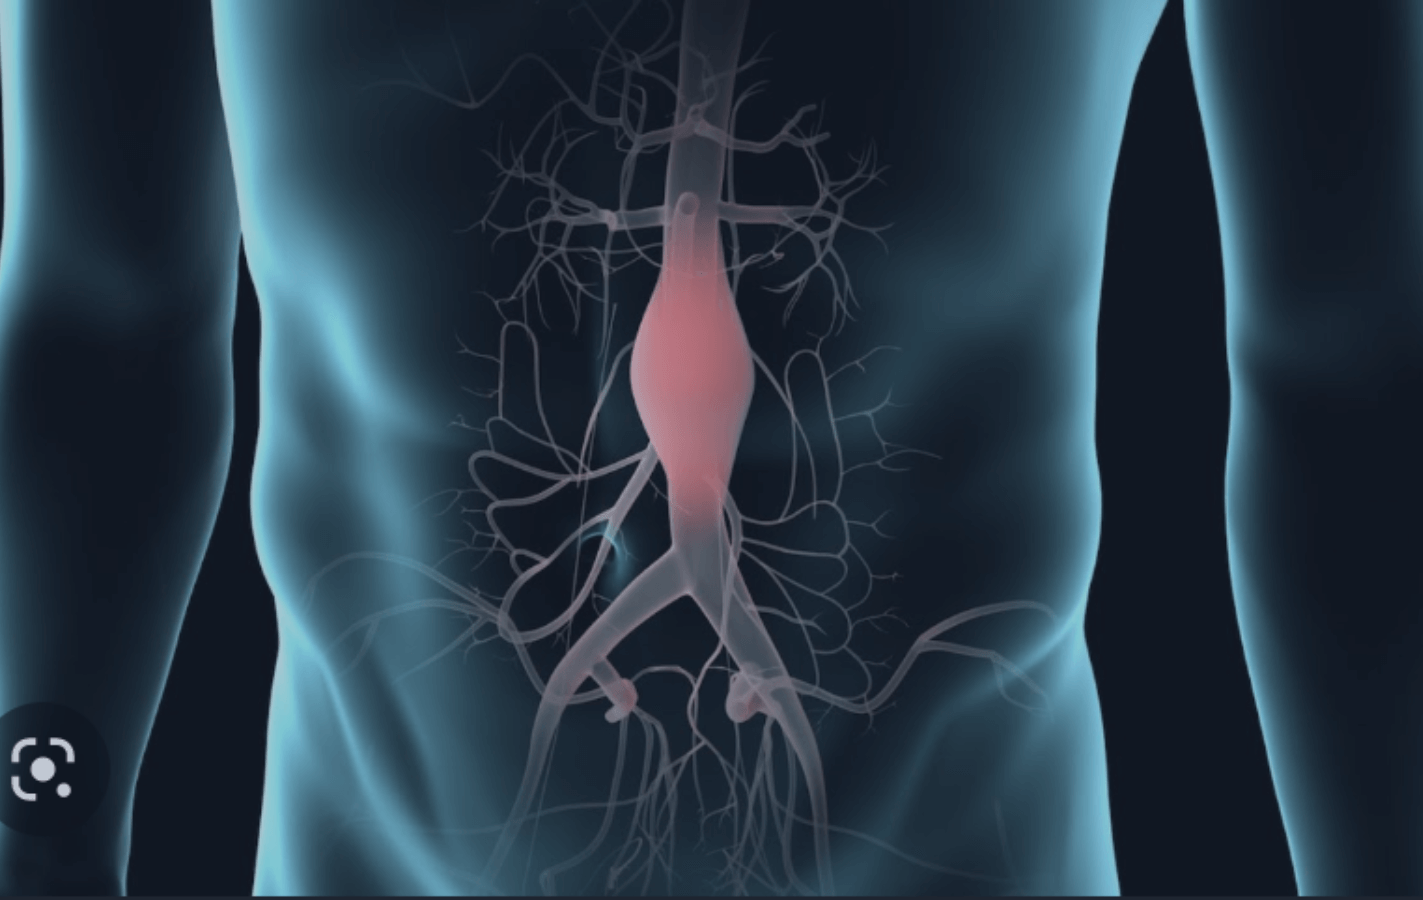

Aneurismas

As artérias do corpo humano podem passar por dois processos de degeneração, as oclusões ou as dilatações. Aneurismas são dilatações dos vasos que deixam a parede desta estrutura cada vez mais delgada a complicação se dá quando esta parede rompe. Nós podemos prevenir, identificar e tratar os aneurismas com a finalidade de evitar maiores problemas.

O QUE É ENDOPRÓTESE PARA ANEURISMA? (Tratamento endovascular do aneurisma da aorta | cateterismo)

Aneurisma da aorta, das artérias ilíacas, artérias poplíteas ou artérias viscerais são dilatações do vaso sanguíneo que ao tornar-se dilatado apresenta uma parede mais frágil que pode romper. Para evitar essa complicação esses aneurismas devem ser tratados e hoje nós dispomos de técnica moderna, efetiva, minimamente invasiva e segura para resolver esse problema com endopróteses.